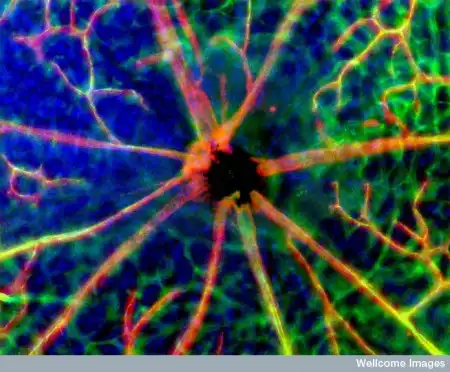

Сеть нейронов головного мозга